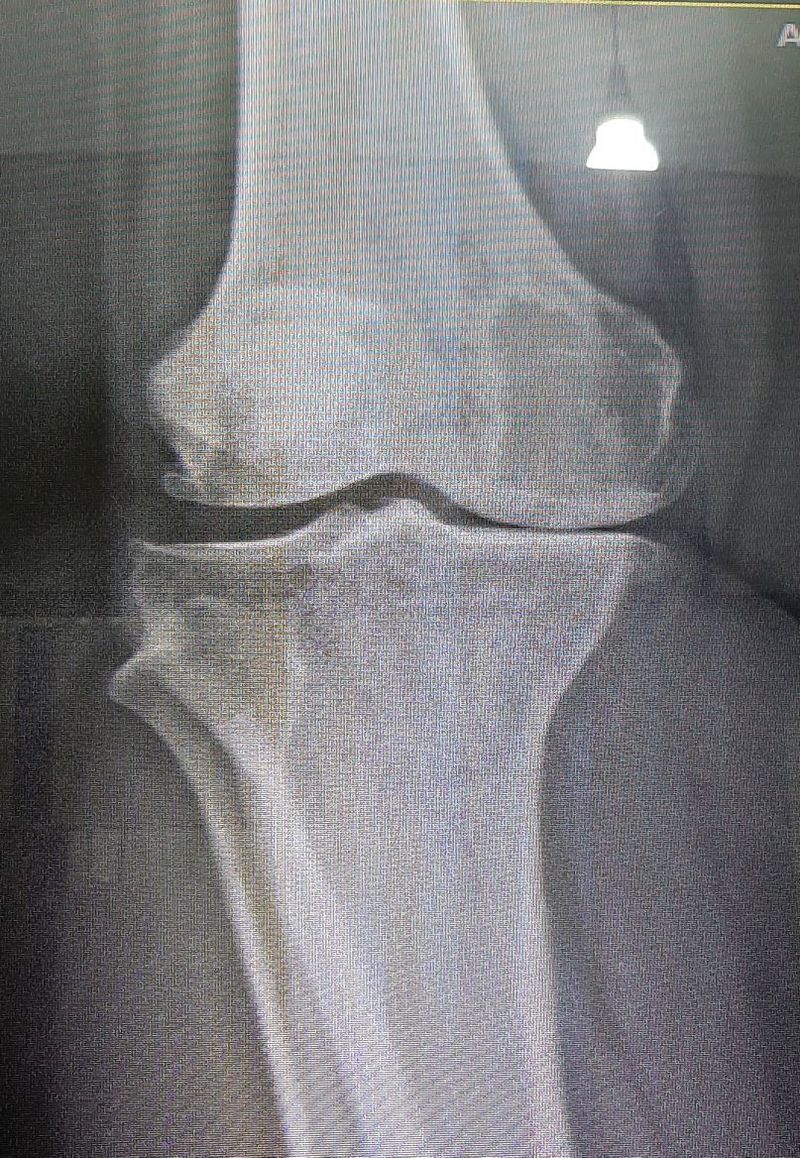

Here's a radiography of a 63-year's-old woman whose chief complaint is knee pain which worsens during walking. Tell the four major radiologic findings, consistent with osteoarthritis. And also, anyone knows the Kellgren's classification of osteoarthritis? Let's review what we know!

One is: the distal part of the phemur is in direct contact with the proximal part of the tibia. I'm trying to use some terminology, I'm in my second week of radiology. So please be gentle ☺

tibial plate sclerosis, flattening of femoral condyles, osteophytes, reduced joint space, cysts in medial condyle